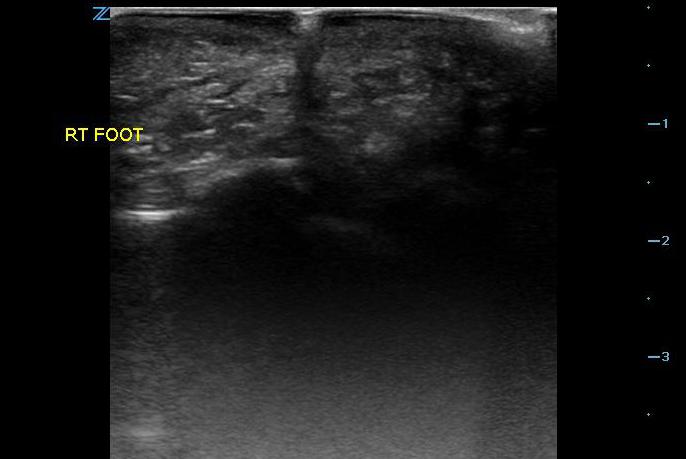

- Figure 2. Glass in foot with shadowing

- The area is scanned throughout its entirety in search for a hyperechoic object in both the sagittal and transverse planes as it can sometimes be much easier to visualize an object in one plane but not the other. Be aware of possible surrounding tissue inflammation or abscess.

- Once a foreign body is localized, the depth from the skin can be measured as well as the size of the object.